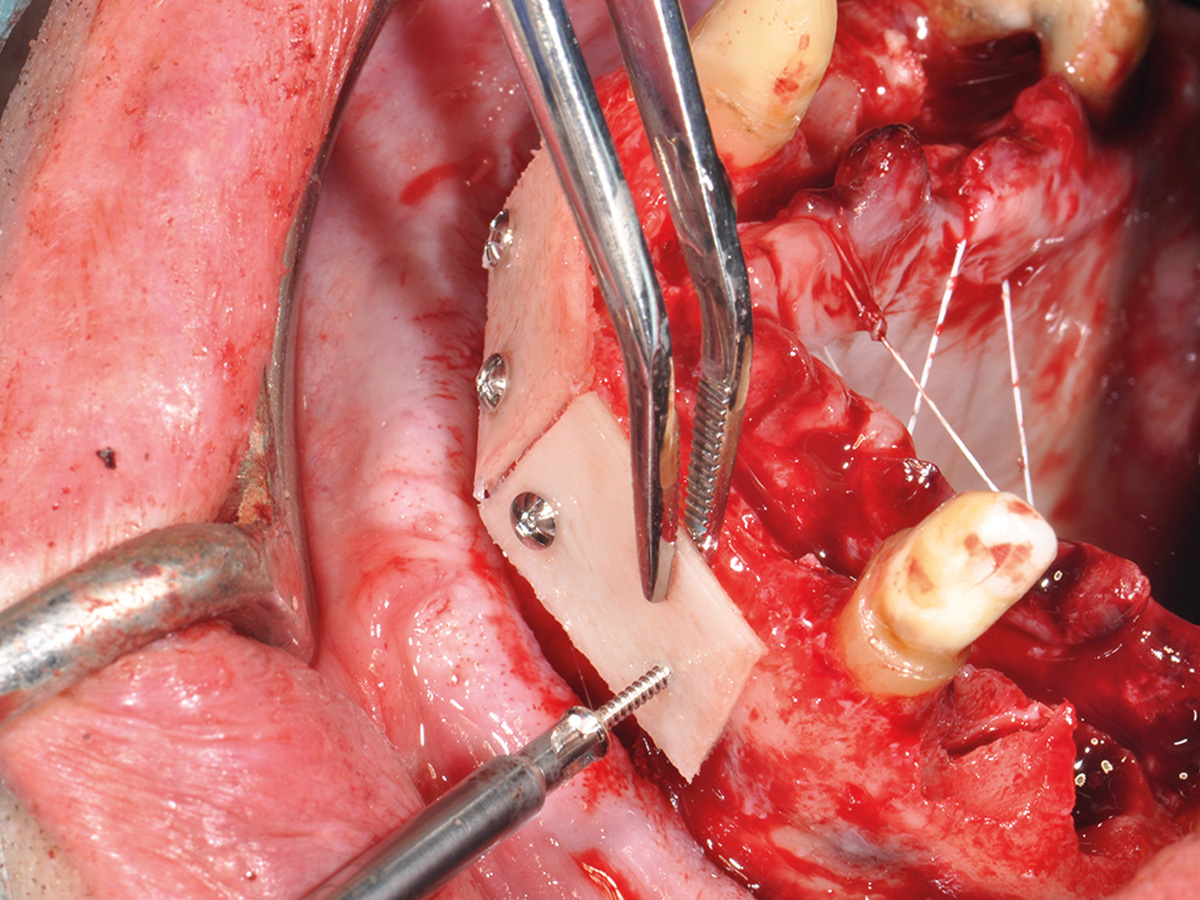

Prinzipien und Konzepte der Knochenaugmentation im Kieferbereich werden logisch aufeinander aufgebaut. Anhand dieser Grundstruktur befähigt der Kurs die Teilnehmer, klinische Situationen fundiert zu analysieren und selbst die logischen chirurgischen Schritte – vom Weichgewebemanagement bis zum Knochenhandling – für die Augmentation abzuleiten.

Im Anschluss werden am Tiermodell alle für eine vorhersehbare Augmentation notwendigen Techniken im Sinne des „Simplify your Augmentation“ eingeübt. Der Weg führt von der einfachen Membrananwendung über die Bone-Lamina- und Double-Layer-Technik bis zur Bone-Shield-Technik. Das Bone Shield ist eine Evolution der klassischen Schalentechnik und erlaubt es, auch komplexe vertikale und kombinierte Augmentationsfälle

im Rahmen der im Kurs vorgestellten Konzeption sicher zu lösen.

Vermittlung des „Simplify your Augmentation“-Konzeptes und Einüben der Bone-Lamina- und Bone-Shield-Techniken am Tiermodell.